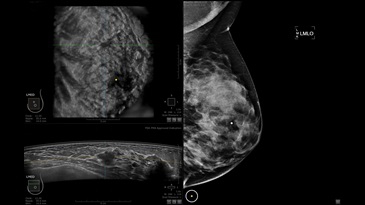

GE INVENIA ABUS – это современный УЗИ аппарат, который создан для точной и эффективной диагностики сканирования с высокой плотностью молочных желез. Выявляемость патологий раковых и предраковых стадий заболевания составляет 55%, что в конечном счете позволяет ставить врачу точные и своевременные диагнозы. Традиционные методы использования маммографии не показывают такой выявляемости, ограничиваясь лишь 3-38%.

УЗИ-аппарат GE INVENIA ABUS позволяет проводить максимально операторонезависимые процедуры, что значительно снижает риск неправильной постановки диагноза и сопутствующие издержки на обработку информации. Система готовит отчет в течение 3-х минут после сканирования, это безусловное преимущество по сравнению с обычным УЗИ сканером.

• Получение объемных 3D изображений с возможностью покадрового просмотра

• Получение изображений в поперечной плоскости (в реальном времени) и в коронарной плоскости (статическая, для указания нахождения соска)

• Отображение объемных 3D ультразвуковых изображений, которые состоят из традиционных поперечных и воссозданных коронарных и сагиттальных проекций

• Стандартизованная ориентация изображения: «толстый срез» в коронарной плоскости; поперечная; сагиттальная плоскость; радиальный и антирадиальный поворот изображения; просмотр исключительно области интереса

• Одновременный просмотр двух изображений для сопоставления в коронарной плоскости